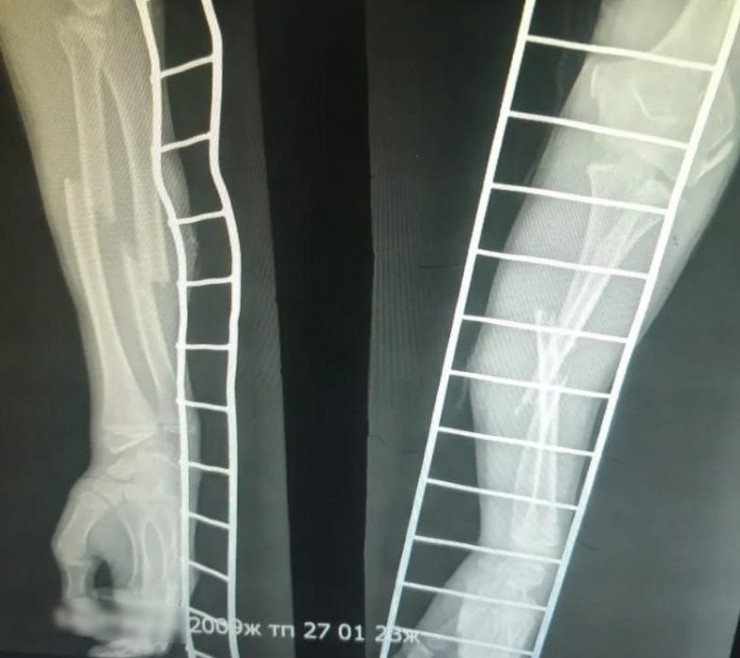

Общественный деятель Дина Тансари сообщила, что у пострадавшего школьника были сломаны две кости. При этом уголовное дело против обидчика не завели, так как он не достиг 14 лет. Также дело не направили в суд по статье 140 УК РК в отношении родителей за "Неисполнение обязанностей по воспитанию несовершеннолетнего".

Фото: t.me/dina_tansari

В пресс-службе полиции Жамбылской области сообщили, что инцидент произошел 27 января в 19:00. Мать ребенка сообщила в полицию 14 февраля, что 13-летний подросток нанес телесные повреждения ее 14-летнему сыну.